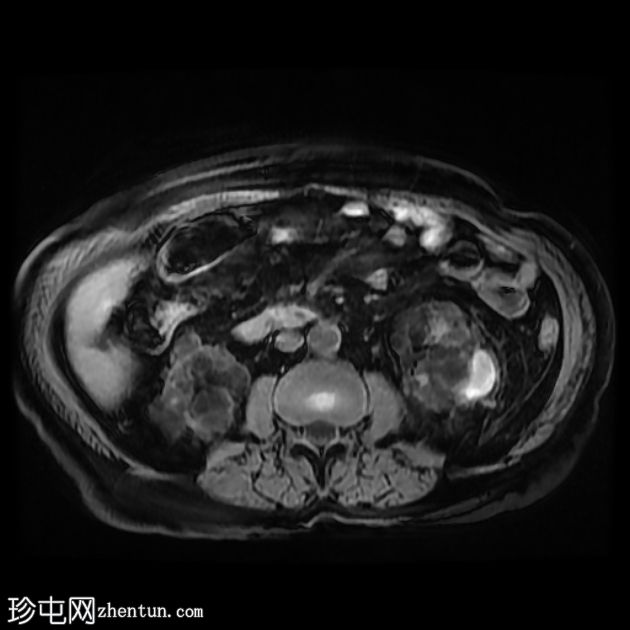

轴位

DWI序列

双侧肾囊性疾病,可见多个肾囊肿,其中许多呈复杂性(出血性)囊肿,T1加权像呈高信号,T2加权像呈低信号。

左侧可见一较大的肾周血肿,与上极出血性囊肿相连,提示出血性囊肿破裂(Wunderlich综合征)。